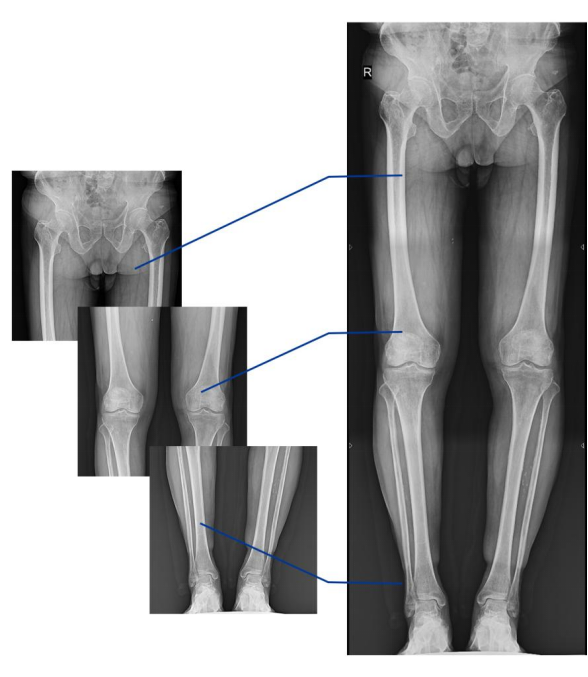

不同于常規靜態DR只能進行平片攝影檢查,動態DR可以滿足多種臨床檢查需求,包括靜態檢查、透視檢查、造影檢查、脊柱及下肢全長拼接檢查,相較于靜態DR具有豐富的臨床應用,且動態DR檢查更精準、直觀,擺位攝片效率極大地提升,大大節省拍片時間。

動態DR影像采集幅面大,17×17英寸超大視野,可覆蓋成年人的全胸全腹,并且能在連續動態中實時高清點片,還可以進行視頻保存,在會診過程中可以回放影像檢查視頻,從而達到精準診斷的目的。同時動態DR還具有全身拼接功能,尤其適用于全脊柱和全下肢攝影,輔助脊柱畸形矯形治療、康復檢查,為臨床提供高精度圖像。